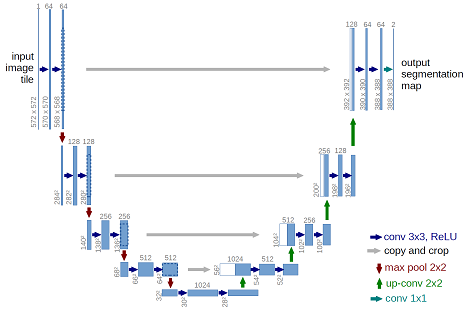

The architecture was inspired by U-Net: Convolutional Networks for Biomedical Image Segmentation.

This deep neural network is implemented with Keras functional API, which makes it extremely easy to experiment with different interesting architectures.

get_unet()inunet.pyto modify the model, optimizer and loss function.